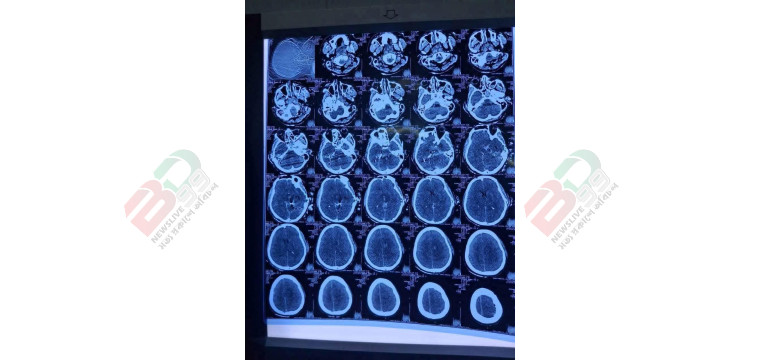

হাদির সিটিস্ক্যানের সর্বশেষ তথ্য দিলেন চিকিৎসক

ঢাকা মেডিকেল কলেজ (ঢামেক) হাসপাতালের জরুরি বিভাগের আবাসিক সার্জন ডা. মোস্তাক আহমেদ বলেছেন, শরিফ ওসমান হাদিকে যখন জরুরি বিভাগে নিয়ে আসা হয় তার অবস্থা খুবই খারাপ ছিল।

পরে হাদিকে সিপিআর দেওয়া হলে এখন একটু প্রেসার ভালো আছে। পরে তার মাথার সিটিস্ক্যান করলে কানের পাশে মাথার ভেতরে গুলি রয়েছে বলে দেখা যায়- তাকে নিউরোসার্জারি ওটিতে নেওয়া হয়েছে।

পরে তাকে সিপিআর (কার্ডিওপালমোনারি রিসাসিটেশন) দেওয়া হয় এবং বর্তমানে প্রেসার কিছুটা স্থিতিশীল।

তার মাথার ভেতরে গুলি রয়েছে এবং কানের আশপাশে গুলি লেগেছে। তাকে নিউরোসার্জারি বিভাগের অপারেশন থিয়েটারে নেওয়া হয়েছে, যেখানে অস্ত্রোপচার চলছে।